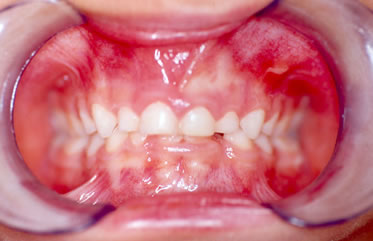

I° Caso- La piccola S.T. di anni 4 è giunta alla nostra osservazione per una visita ortodontica mandata dal suo pediatra di famiglia. All'anamnesi risultava che la bambina respirava prevalentemente con la bocca e durante la notte russava e andava i apnea. All'esame clinico ortodontico la bambina presentava un morso inverso anteriore con palato ogivale (Figura 1).E' stato richiesto quindi un monitoraggio cardio-respiratorio che è stato eseguito con un poly-mesam 8 canali portatile. Tale esame ha evidenziato un RDI =13 associato a forte russamento (Figura 2). Sulla radiografia del cranio in proiezione latero-laterale è stata eseguita l'analisi cefalometrica che ha messo in evidenza una I classe scheletrica con tendenza alla III in soggetto ipodivergente. In considerazione del morso inverso e del palato ogivale, si è deciso di applicare un espansore rapido palatale con ganci per maschera di Del aire (Figura 3). Ottenuta l'apertura della sutura palatina è stata applicata la Maschera facciale di Delaire per la trazione postero-anteriore del mascellare superiore. Dopo 2 mesi dall'inizio della terapia è stato eseguito un monitoraggio cardio-respiratorio di controllo che ha messo in evidenza un RDI= 5 con riduzione del russamento rumoroso (Figura 4). Dopo 6 mesi, ottenuta la correzione del morso inverso e del palato ogivale, una volta rimosso l'espansore rapido e la maschera facciale, è stato applicato un apparecchio funzionale di III classe come mantenimento. La correzione della malocclusione ha coinciso con il miglioramento dei sintomi respiratori come anche riferito dalla madre.

Figura 1: Paziente S.T. di anni 4 dove si evidenzia un morso inverso e palato ogivale.